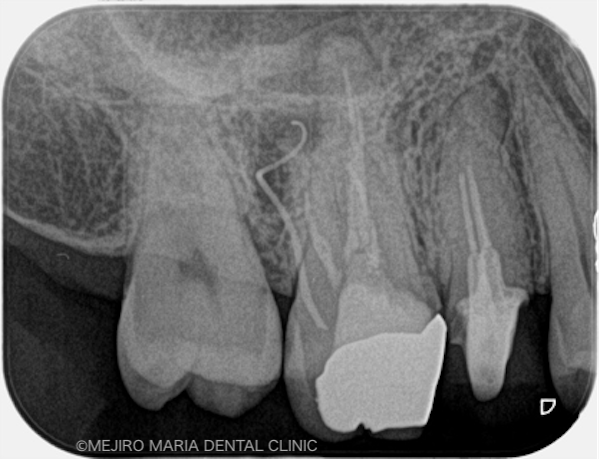

|治療詳細1.jpg)

右上6番の歯に確認できたフィステル(瘻孔)は、2回目の根管治療の際にはすでに消失していました。患者様のご希望により、すでに根管治療がされている手前側の歯(右上5番)も、根管治療をやり直すこととなりました。